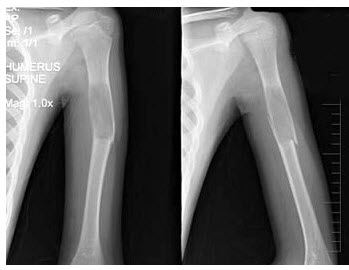

289、单项选择题

男,8岁,左上臂外伤后疼痛2小时,结合左肱骨正、斜位片,最可能的诊断为()

A.骨肉瘤

B.尤因肉瘤

C.骨囊肿

D.骨嗜酸性肉芽肿

E.非骨化性纤维瘤